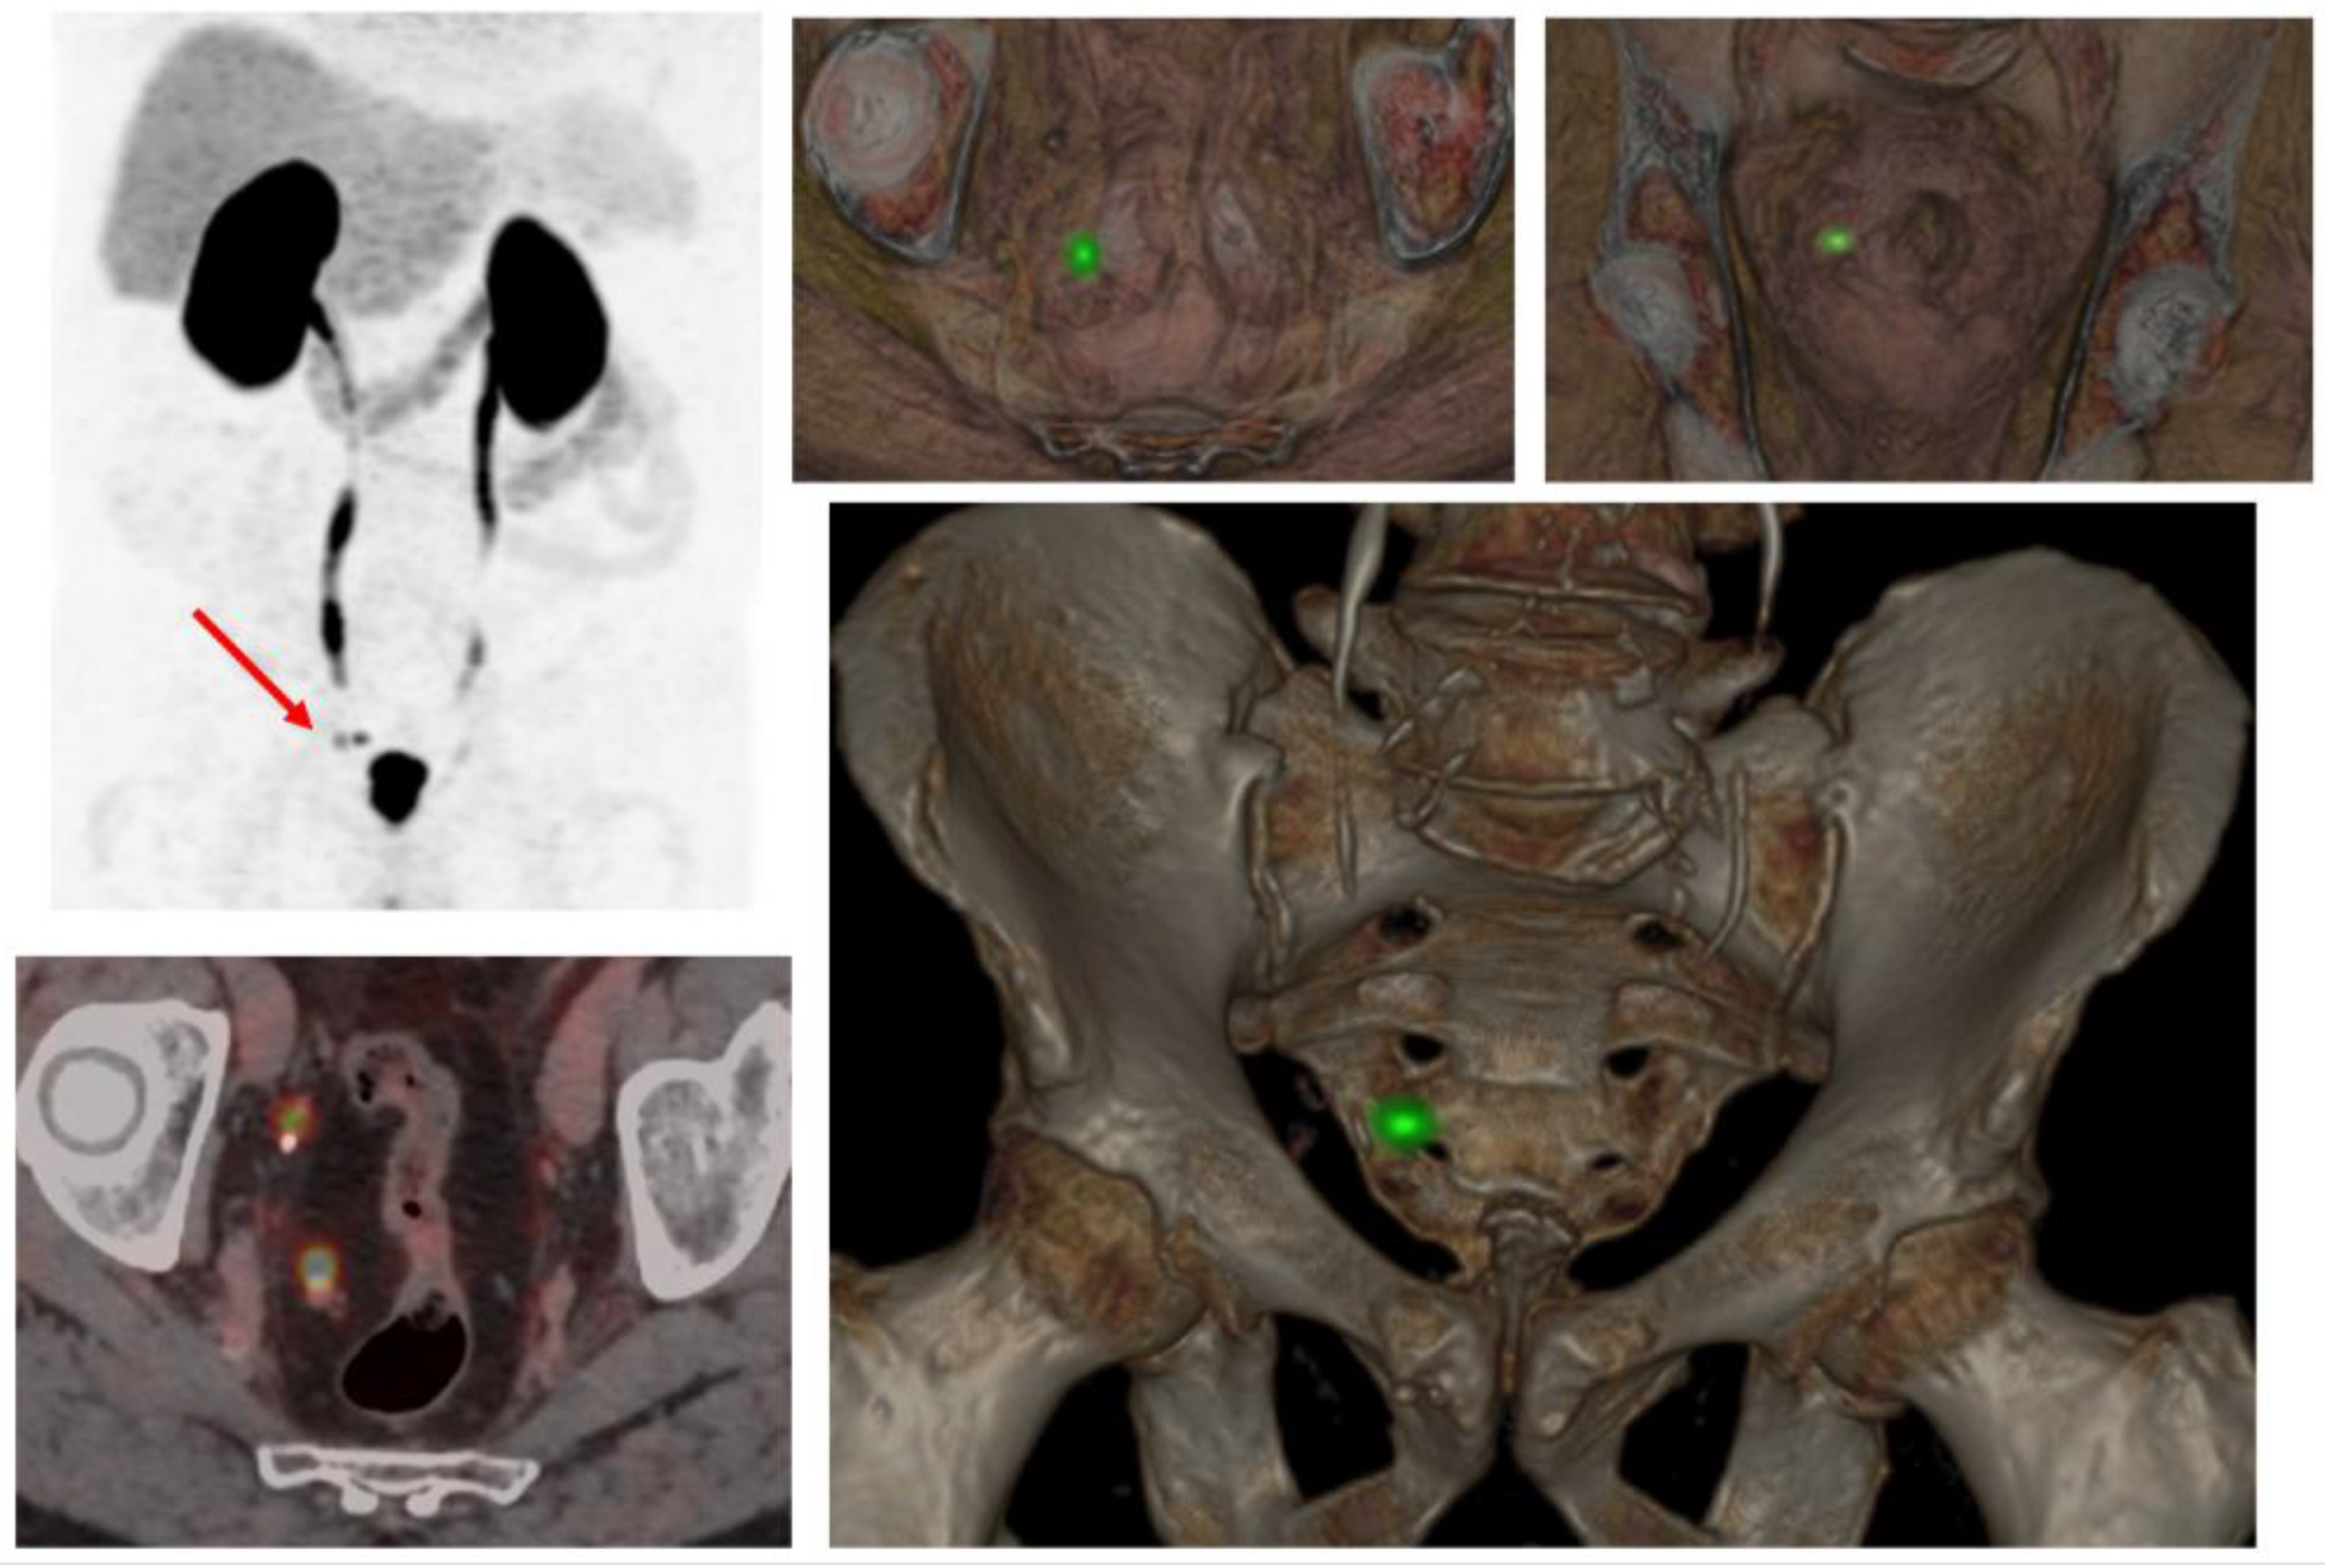

4.2. PSMA-PET/CT in Metachronous Oligometastatic Disease and MDT

- Awiwi, M.O.; Gjoni, M.; Vikram, R.; Altinmakas, E.; Dogan, H.; Bathala, T.K.; Naik, S.; Ravizzini, G.; Kandemirli, S.G.; Elsayes, K.M.; et al. MRI and PSMA PET/CT of Biochemical Recurrence of Prostate Cancer. Radiographics 2023, 43, e230112. [Google Scholar] [CrossRef] [PubMed]

- Sonni, I.; Dal Pra, A.; O'Connell, D.P.; Ells, Z.; Benz, M.; Nguyen, K.; Yoon, S.M.; Deng, J.; Smith, C.; Grogan, T.; et al. 68Ga-PSMA PET/CT-Based Atlas for Prostate Bed Recurrence After Radical Prostatectomy: Clinical Implications for Salvage Radiation Therapy Contouring Guidelines. J. Nucl. Med. 2023, 64, 902–909. [Google Scholar] [CrossRef]